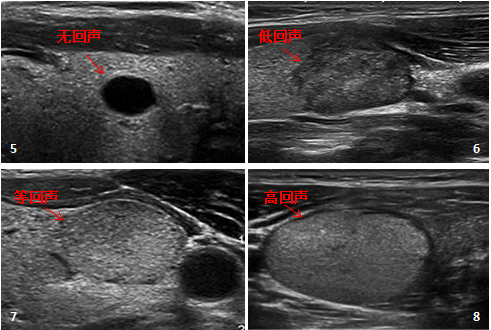

甲状腺结节超声征象的区别

甲状腺彩超报告关于位置、大小、形态、边缘、回声、血流等的描述,是给临床医生诊断患者的重要信息。